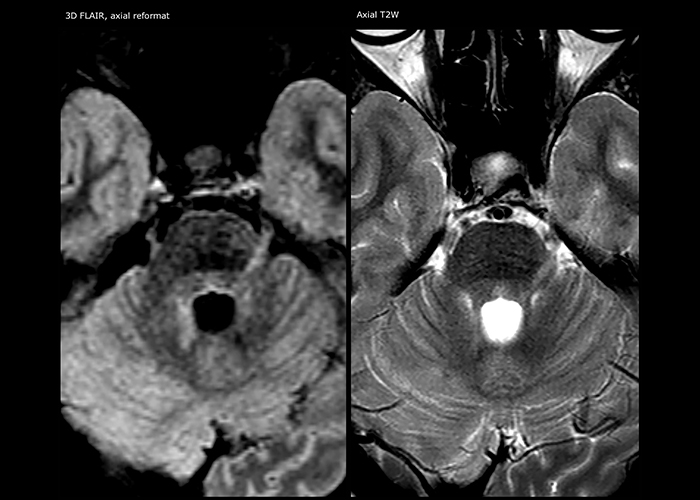

Imaging MS in brain

For MS imaging in the brain, Dr. Savatovsky uses 3D FLAIR as the basic sequence to visualize the lesions and assess the situation and lesion load. “We count the lesions in each location to determine if the criteria of the disease are fulfilled. We use a T2-weighted sequence because our neurologists are used to it. We compare the lesion load on FLAIR with a 3D T1 post-contrast sequence to help us determine whether lesions are old or new. We typically administer the contrast before the patient enters the machine because it shortens the examination time and allows to visualize active lesions that tend to be more visible after several minutes. When a differential diagnosis is difficult, we add sequences such as susceptibility imaging, because some focal MS lesions have a small vein in the center[3].”

MS imaging in spine is more complicated

“For MS imaging in the spine, the basic examination includes a sagittal T2 and a post-contrast sagittal T1-weighted sequence in the whole spine. These are done in two stacks and using thin slices, for example 2 mm, without gap. As in the brain, the T2-weighted sequence visualizes the overall lesion load and helps determine if lesions are old or new. The post-contrast T1- weighted sequence helps in assessing if a lesion is new. We will sometimes add a T1 inversion recovery sequence, which has very good sensitivity, if we don’t find any lesions on T2,” Dr. Savatovsky says. “Additionally, if there is contrast enhancement outside the spine, it’s usually not MS but another kind of inflammation.”